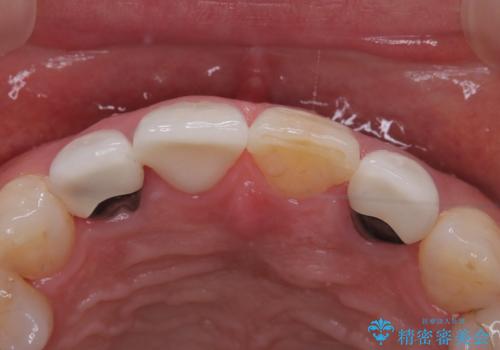

隣と同じように白くしたい、再治療を減らしたいとのことで、セラミッククラウン(スペシャル)で治療することとなりました。

治療回数を減らしたかったため、虫歯をとり形成を行い仮歯への置き換えとともに型どりを行いました。